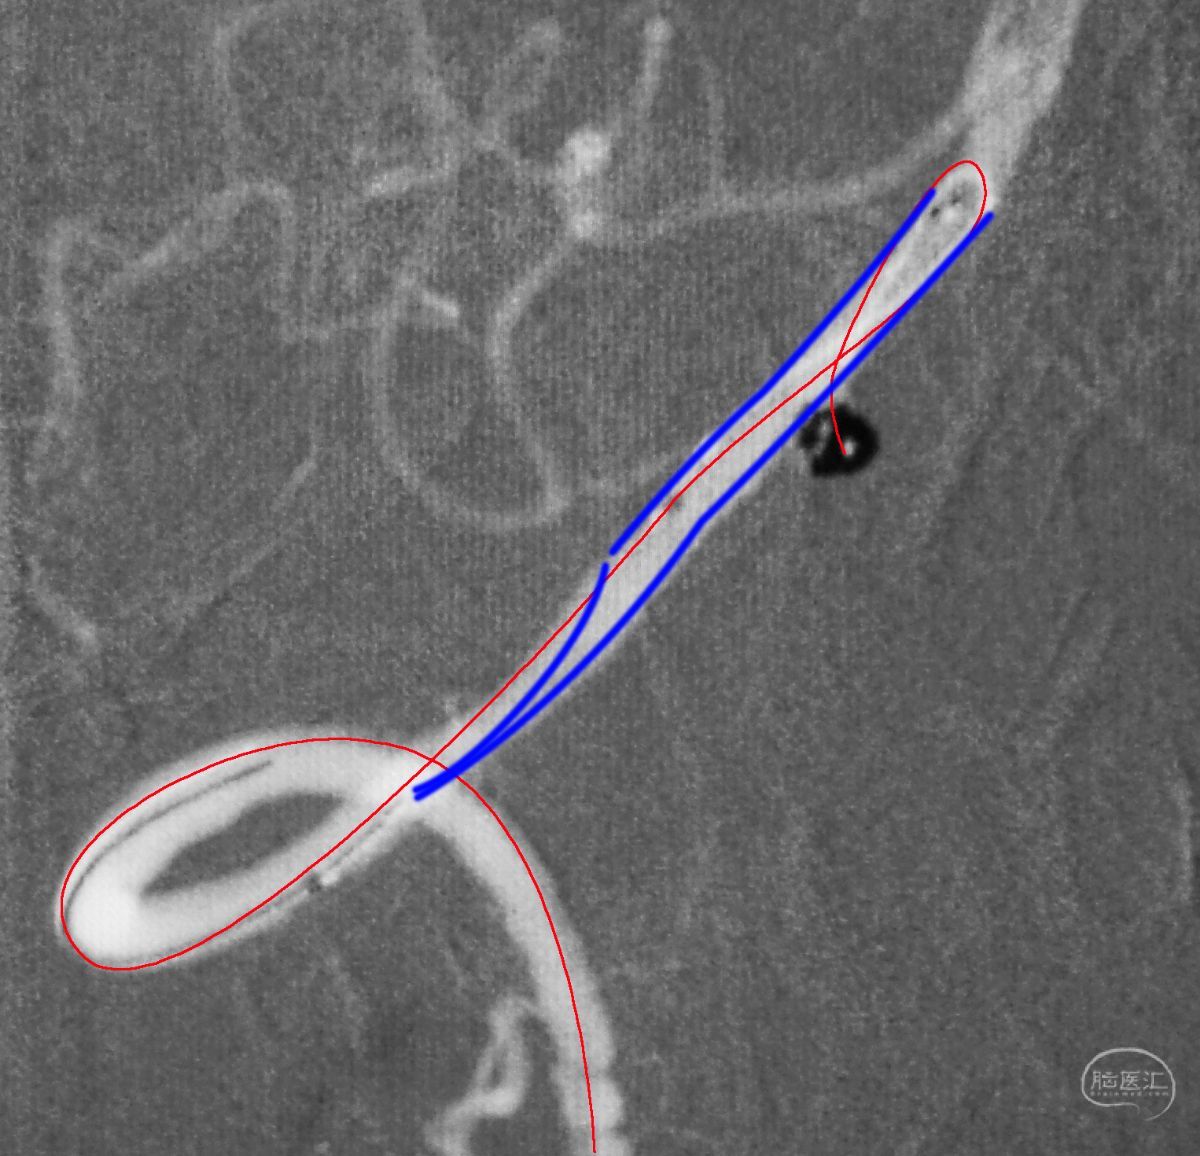

Echelon 10微导管头无论塑成C形还是S形,均无法稳定于动脉瘤腔内,遂使用回马枪技术,使微导管成襻通过,管头折返入瘤腔。

跨瘤颈释放Solitaire 4×20支架(蓝线),压住微导管(红线),在支架保护下经返折的微导管送入弹簧圈填塞瘤腔。